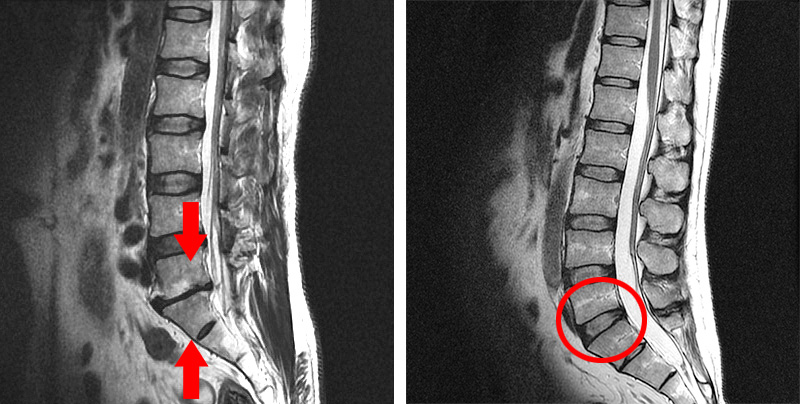

첫 번째 경우는 X-ray나 MRI 검사결과를 보고 디스크의 높이가 낮아진 것을 협착이라고 착각하는 경우입니다. 디스크가 퇴행되었거나 또는 디스크가 탈출되어 수핵이 빠져나가면 디스크의 높이가 낮아지는데, 디스크의 높이가 낮아지면 '디스크가 눌려서 압착되어 있으니까 이게 협착이구나' 하고 착각하게 되는 것 같습니다. 사실 협착이라는 단어는 일상생활에서 잘 쓰지 않는 단어이기 때문에 눌려서 압착되어 있는 걸 협착이라고 오해하는 것이죠. 그러나 디스크에 퇴행성 변화가 발생하여 디스크의 높이가 낮아진 것은 협착이 아니라, 그냥 허리디스크입니다. 협착이라는 것은 디스크를 옆에서 봤을 때 디스크가 눌린 게 아니고, 척추관이 좁아진 것을 말합니다.

척추관이 좁아지게 되면 MRI로도 많이 좁아진 게 보이며, 반대로 협착증이 아닌 경우에는 MRI 상으로도 공간이 넓습니다. 따라서 단순히 디스크의 높이가 낮아진 것을 보고 이걸 협착이라고 착각하시면 안 됩니다.

협착의 정확한 뜻은 어떤 관이나 구멍, 또는 이와 유사한 구조물들의 안쪽 폭이 좁아진 상태를 뜻합니다. 그래서 사전적인 의미로만 본다면, 당연히 디스크만 밀려나와도 척추관 구멍의 넓이는 좁아집니다. 그러나 이렇게 디스크가 밀려나와서 척추관이 좁아졌다고 해도 이것을 협착증이라고 진단할 수 있는 것은 아닙니다. 디스크가 밀려나온 것은 그냥 허리디스크지, 협착증이 아닙니다. 한 10년 전만 하더라도 이렇게 밀려나온 디스크로 척추관이 좁아지면, 좁아진다는 의미로써 narrowing이라는 단어를 많이 썼는데, 최근 몇 년 사이 좁아졌다는 표현보다는 '협착'이란 단어를 의사들이 훨씬 더 많이 써서 표현하고 있습니다. 이렇듯 의료진들이 디스크 때문에 척추관이 좁아졌다는 의미로 협착이란 단어를 쓰면, 환자들은 '아 내가 협착증이구나' 하고 오해하게 됩니다. 따라서 디스크가 밀려나와서 척추관이 좁아졌다는 의미로 협착이란 말을 진료 시에 쓰는 것은 바람직한 현상이 아니라고 저희는 생각하고 있습니다. 왜냐하면 허리디스크인 환자가 협착증이라고 잘못 오해하게 되면, 협착증에 맞지 않는 잘못된 운동을 할 수 있고, 또한 잘못된 치료로 이어질 수 있기 때문입니다. 예를 들면 저희는 협착증 환자분들에게는 맥켄지 운동을 하지 말라고 말씀 드리는데, 간혹 본인은 맥켄지 운동을 하니까 좋은 것 같다고 말하는 경우가 있습니다. 이런 분들은 협착증 진단이 제대로 되었는지 확인할 필요가 있습니다. 협착증 환자가 맥켄지 운동을 하면 안 되는 이유에 대한 자세한 내용은 아래 영상을 보시길 바랍니다.